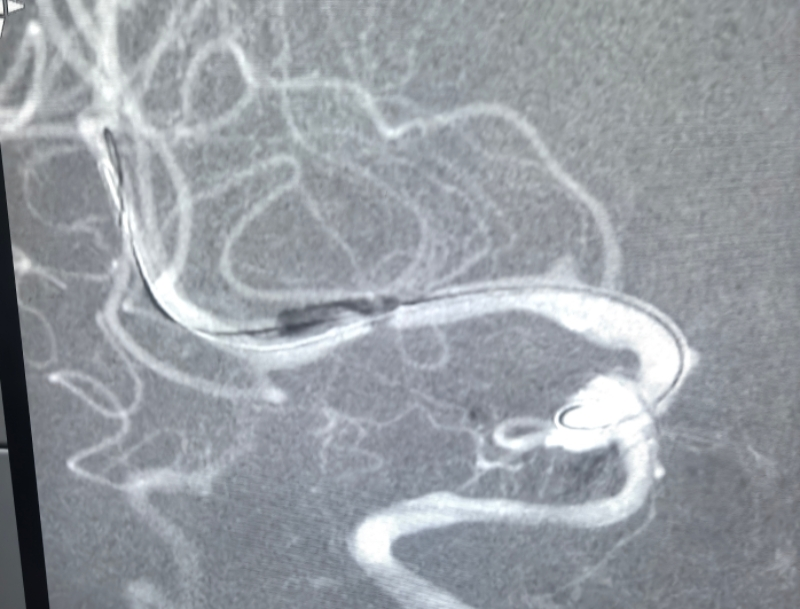

术前,影像科师毅冰主任团队已完成精准筛查,为手术方案制定提供了详实的影像学依据;手术当日,神经血管介入MDT团队傅新民主任凭借丰富的临床经验和精湛的操作技术,由导管室护士长张学萍安排手术间、朱春婷导管室护师精心协助下,历时 1 小时完成精准治疗 —— 先以小球囊对狭窄血管段进行逐步扩张,再成功释放颅内支架,全程操作规范、精准高效,最大限度保护了患者正常脑组织供血。

麻醉环节是此次救治的关键保障。麻醉科科主任王立伟主任指示、高星医师全程坚守岗位,根据患者病情特点及手术流程,精准制定麻醉方案,灵活调整用药剂量与给药时机。手术中,她严密监测患者生命体征、麻醉深度及脑血流灌注情况,确保手术过程中患者生命体征平稳;术后,在导管室临时复苏区域,高星医师凭借扎实的专业功底和丰富的复苏经验,精准调控复苏药物,密切观察患者意识、呼吸及神经功能恢复情况,确保患者平稳苏醒。当患者醒来后,经检查四肢活动正常,无新增神经功能缺损症状,在场医护人员均松了一口气。